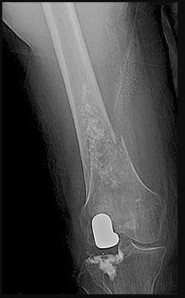

Question 24

A 14-year-old boy presents with a painful, swollen thigh. Radiographs reveal a permeative, diaphyseal lesion of the femur with an extensive 'onion-skin' periosteal reaction.

A core needle biopsy is performed. Which of the following chromosomal translocations and resulting fusion proteins is most characteristic of this tumor?

Explanation

The clinical and radiographic presentation is classic for Ewing sarcoma. Ewing sarcoma is a small round blue cell tumor most commonly arising in the diaphysis of long bones in children and adolescents. It is defined by the t(11;22)(q24;q12) translocation in ~85% of cases, which produces the EWS-FLI1 fusion protein. SYT-SSX is associated with synovial sarcoma. TLS-CHOP is seen in myxoid liposarcoma. PAX3-FKHR is seen in alveolar rhabdomyosarcoma.